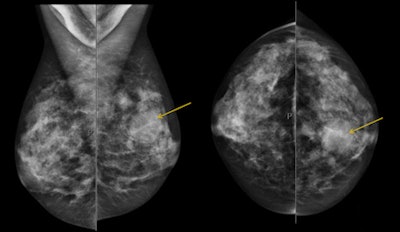

| 46-year-old patient presents for evaluation of left breast nodule after being recalled from screening mammography. Above, mammogram: Nodule present within the left central aspect. Below, B-mode and elastography: Ultrasound shows a cyst present corresponding to area noted on mammogram. Elastography image demonstrates the "bull's-eye" appearance of cysts on elastography. A cyst aspiration was performed and the cyst resolved. Images courtesy of Dr. Stamatia Destounis. |